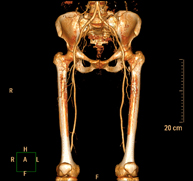

- Angio-TC arterial d'extremitats inferiors Prova diagnòstica no invasiva que consisteix en l'estudi vascular del sector aorto-ilíac i dels vasos arterials d'ambdues extremitats inferiors i l'obtenció d'imatges d'alta definició anatòmica mitjançant l'ús d'un equip de TC Multidetector d'última generació i de contrast iodat. La qualitat de les imatges permet realitzar reconstruccions en 2D i 3D gràcies a estacions de treball especialitzades en l'estudi arterial. Prova diagnòstica no invasiva que consisteix en l'estudi vascular del sector aorto-ilíac i dels vasos arterials d'ambdues extremitats inferiors i l'obtenció d'imatges d'alta definició anatòmica mitjançant l'ús d'un equip de TC Multidetector d'última generació i de contrast iodat. La qualitat de les imatges permet realitzar reconstruccions en 2D i 3D gràcies a estacions de treball especialitzades en l'estudi arterial.

- Angio TC arterial d'extremitats inferiors Prova diagnòstica no invasiva que consisteix en l'estudi de vascular del sector aorto-ílíac i dels vasos arterials d'ambdues extremitats inferiors amb l'obtenció d'imatges d'alta definició anatòmica mitjançant l'ús d'un equip de TC (Tomografia Computaritzada) i contrast iodat. La qualitat de les imatges permet realitzar reconstruccions en 2D i 3D gràcies a estacions de treball especialitzades en l'estudi arterial. Prova diagnòstica no invasiva que consisteix en l'estudi de vascular del sector aorto-ílíac i dels vasos arterials d'ambdues extremitats inferiors amb l'obtenció d'imatges d'alta definició anatòmica mitjançant l'ús d'un equip de TC (Tomografia Computaritzada) i contrast iodat. La qualitat de les imatges permet realitzar reconstruccions en 2D i 3D gràcies a estacions de treball especialitzades en l'estudi arterial.